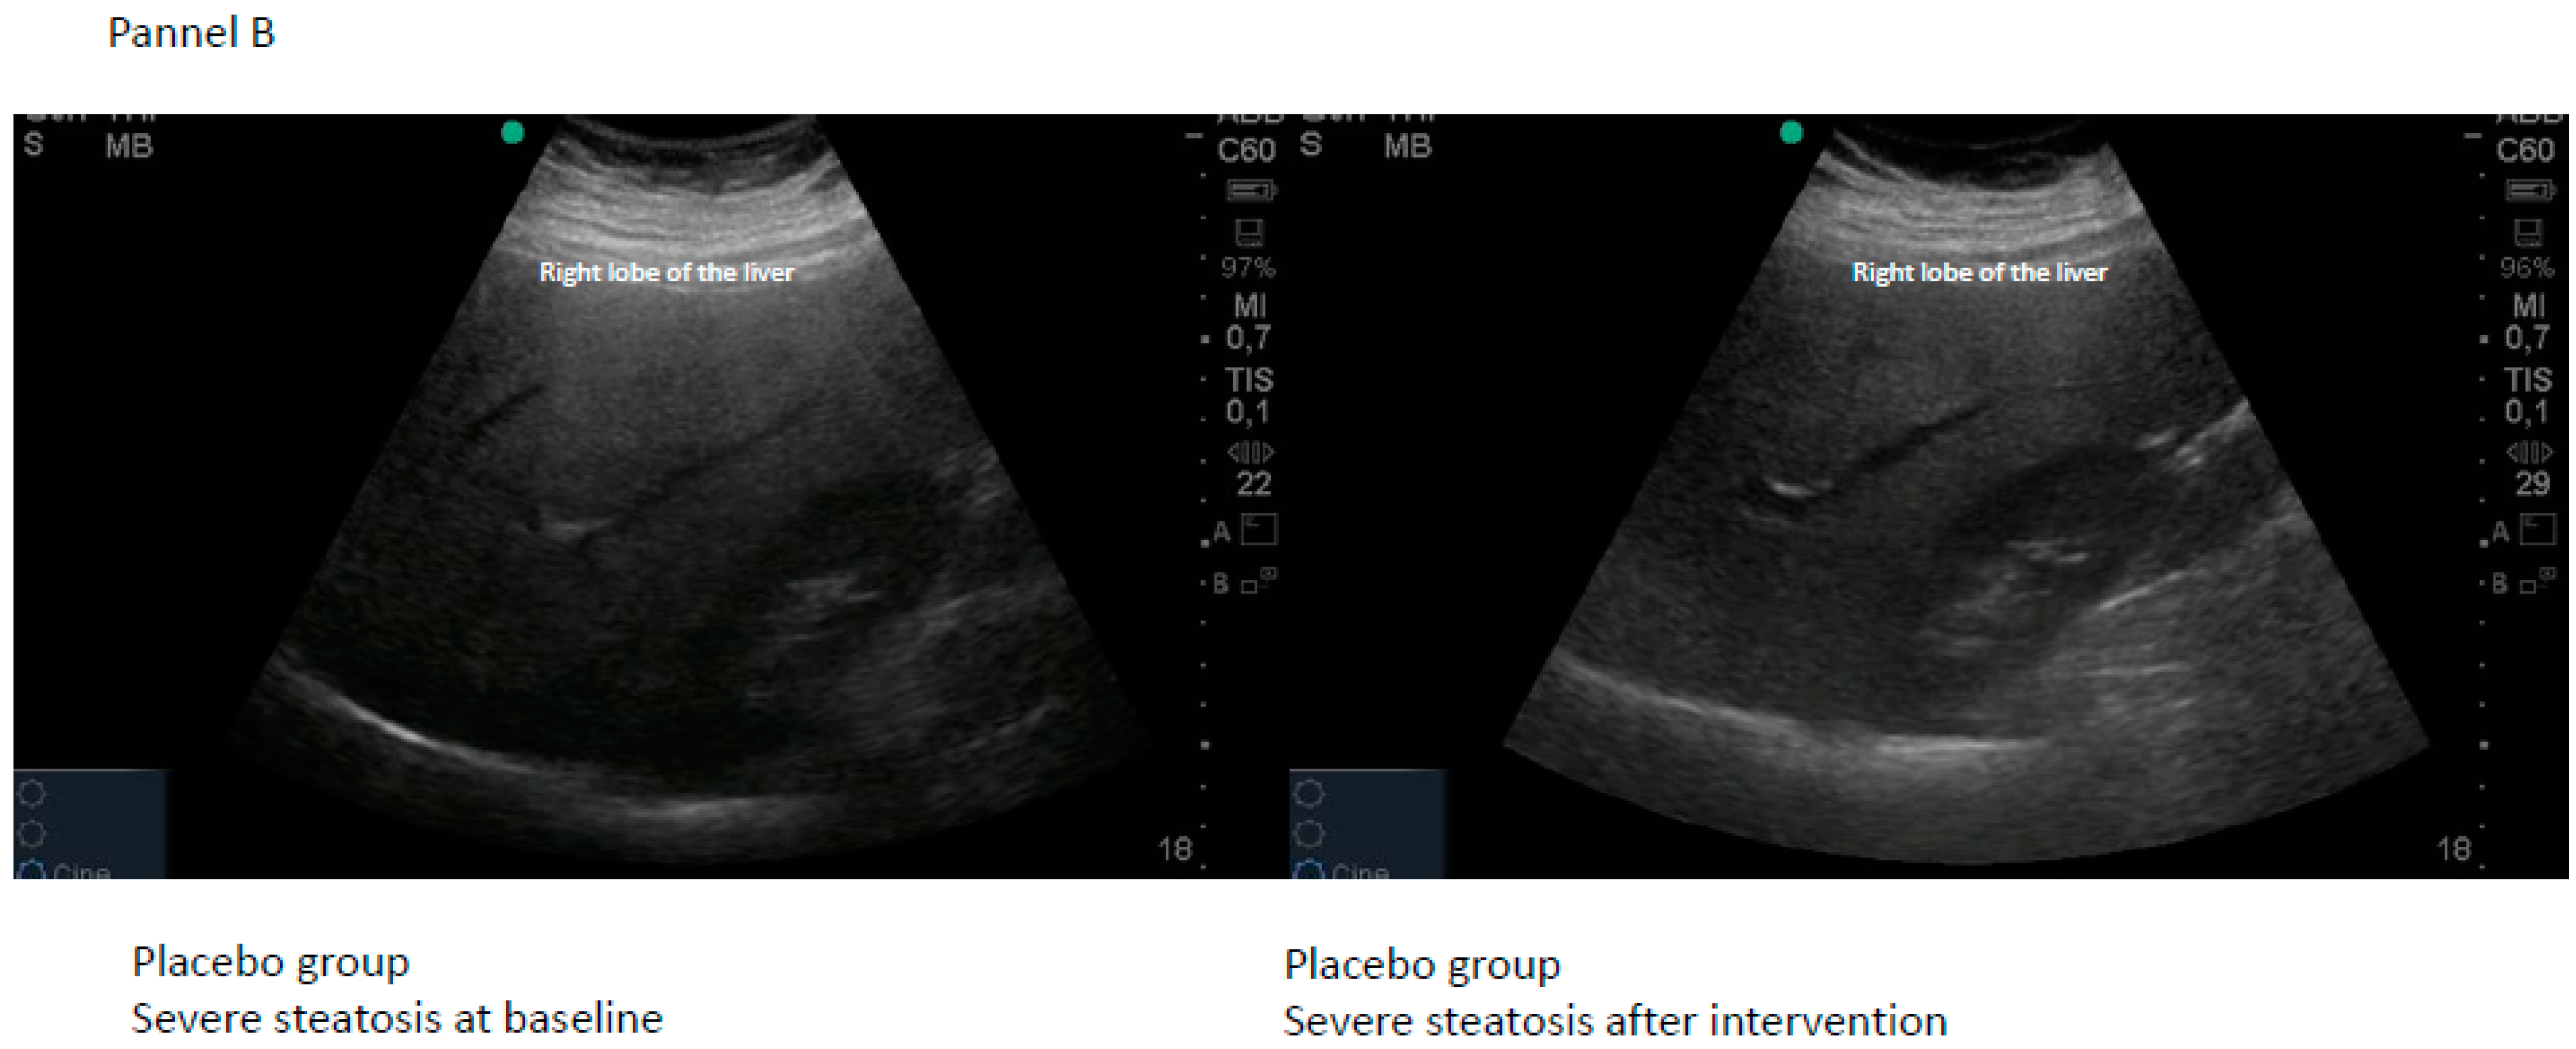

| Citrulline | Final Steatosis | |||||||

|---|---|---|---|---|---|---|---|---|

| n = 22 | Normal | Mild | Moderate | Severe | Total | Chi-Square | p | |

| Baseline steatosis | Mild | 8 | 2 | 0 | 0 | 10 | 11.589 | 0.0007 |

| Moderate | 1 | 1 | 6 | 0 | 8 | |||

| Severe | 0 | 0 | 2 | 2 | 4 | |||

| Total | 9 | 3 | 8 | 2 | 22 | |||

| Placebo | Final steatosis | |||||||

| n = 20 | Normal | Mild | Moderate | Severe | Total | Chi-square | p | |

| Baseline steatosis | Mild | 3 | 3 | 0 | 0 | 6 | 1.633 | 0.2013 |

| Moderate | 3 | 3 | 6 | 0 | 12 | |||

| Severe | 0 | 0 | 1 | 1 | 2 | |||

| Total | 6 | 6 | 7 | 1 | 20 | |||